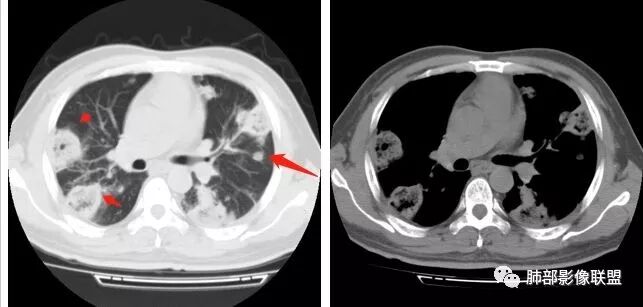

南边:胸膜下,类圆形,边界清,内有坏死,典型的反晕征,支气管壁增厚不明显,支持血道来源脓毒栓子所致梗死、感染

南边:反晕征是毛霉菌的特点按理单从影像:毛霉菌更多符合因为细菌性的特点:液气平面,囊,这个没出现

肺克的影像表现(唐绍宏总结):分布:单侧上叶病变,以右肺上叶多见;患者长期卧床则双脚下肺后基底段分布(国外下肺多见,可能与平均寿命长,卧床及住托老机构多有关) ;如多叶段病变,则以肺上叶后段或下叶后基底段为最明显形态:气管壁增厚、磨玻璃、小叶实变、节段实变、大叶实变,坏死小空洞(直径小于2cm) ,少量胸腔积液50%、脓胸20%特点:早期气管壁增厚较明显、广泛,越靠近病灶越明显,越靠近肺门越明显,见于实变病灶外,偶尔见于磨玻璃影内(支气管通气征) ;未经抗生素治疗,实变病灶内无支气管通气征;早期即可出现坏死,无论坏死还是空洞,绝大多数直径小于2cm (可能与此菌有厚夹膜有关,参考隐球菌)